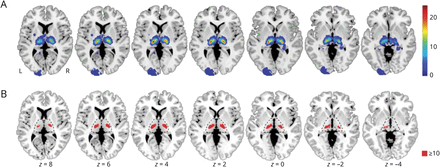

与无语言障碍的患者相比,VLSM发现左侧背中丘脑核(102体素,MNI:−12,−15,1)存在显著相关性。右侧运动和感觉缺陷分别与对侧(左)腹侧侧核(819体素,MNI:−17,−21,2)、腹侧侧核和后外侧丘脑核(660体素,MNI:−17,−20,3)相关。尽管与语言相关的区域在空间上与与右侧运动或感觉缺陷相关的区域分离,但后两者在腹侧核重叠(图3).左运动(871体素,MNI: 15,−17,4)和感觉障碍(894体素,MNI: 17,−19,3)在对侧(右)腹外侧和后外侧核中出现镜像模式。构音障碍未发现相关。将病变体积作为分析中不感兴趣的协变量添加,并没有改变结果(未显示)。

基于体素的病变-症状映射,对比语言障碍和运动或感觉缺陷患者的病变。所有分析均采用非参数Liebermeister试验,阈值为p(FWE) < 0.05。仅显示相应症状的重要体素。与没有语言障碍的人相比,语言障碍与左侧中背丘脑核(青色)有关。运动和感觉缺陷分别映射到对侧腹侧(红色)和后外侧(绿色)丘脑核。这些突起部分重叠于丘脑腹侧核。每个比较包括所有101例患者,例如,右侧运动缺陷患者与所有其他无右侧运动缺陷的患者(包括左侧运动缺陷患者)进行比较。解剖标记基于人类丘脑的概率图谱,显示为基于体素的病变-症状映射结果旁边的参考;虚线标记丘脑核的边界。18代表性轴向切片位于MNI空间;z坐标报告在图像下方。FWE =家庭错误;蒙特利尔神经学研究所。

本研究中纳入的患者病变分布于两侧丘脑。与其他研究一致,根据外侧丘脑是最常见的病变位置,腹外侧丘脑最常受影响(图2一个)。24,25前内侧和后内侧丘脑核受影响的频率较低,因此不能纳入VLSM分析,尽管先前的病例研究结果确实报告了这些核病变后的丘脑失语症(表1,links.lww.com/WNL/C447).作为主要结果,VLSM分析显示,与构音障碍和运动或感觉障碍患者相比,语言障碍患者左侧背中核更容易受损(图3青色)。后两种表现出与语言障碍在空间上截然不同的损伤-症状关联(图3(红色和绿色),并与先前腹侧和后外侧核参与运动和躯体感觉的证据一致。26虽然与报告左侧背中核累及丘脑失语症的病例研究一致(表1),但我们的研究基于更大样本的体素统计比较提供了额外的经验证据。基于任务的功能磁共振成像也证实了左背中核对语言的贡献,表明其在语义记忆和词汇-语义处理中发挥作用。27,-,29几项功能磁共振成像研究显示,丘脑峰分布的可视化显示左侧靠近中线区域(板内核和背中核)的聚类,特别是在感知挑战性的语言任务中。30.这可能与执行功能和语言功能之间的重叠有关,例如,对语言处理的领域一般执行控制可能会随着任务需求的增加而发挥作用。31,-,33在这种情况下,认知的调节作用一般被归因于背中核。8,34与此一致,一项损伤研究表明,丘脑背中核损伤导致执行功能受损,并提出丘脑皮质网络功能障碍导致这些缺陷。35在接下来的文章中,我们将讨论LNSM结果,特别关注涉及语言和领域通用网络的识别模式。